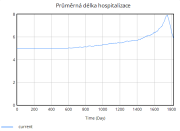

| 22:34, 15 June 2025 | 1 DelkaHospitalizace.png (file) |  |

11 KB | Kozo01 | 1 | |